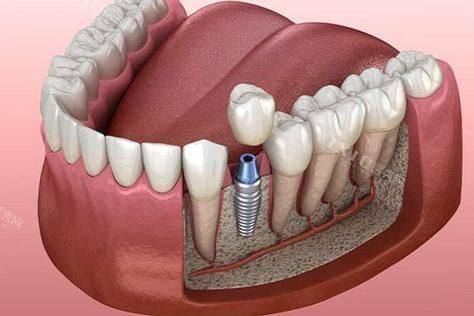

种植牙:通过种植体修复缺失牙齿,修复正常咀嚼功能与美观成效。

浙江金华永康雅尔口腔 单颗种植牙:3999元起

刘先生 | 种植牙

“我前阵子掉了一颗后牙,吃饭都不方便,在网上查到雅尔口腔是永康前十的牙科机构,就来询问种植牙。医生给我做了详细的口腔检查,推荐了适合我的种植方案,手术过程比我预想的轻松特别多,现在种植牙用了三个多月,咀嚼功能修复得良好,感谢医生团队的专精技术。”